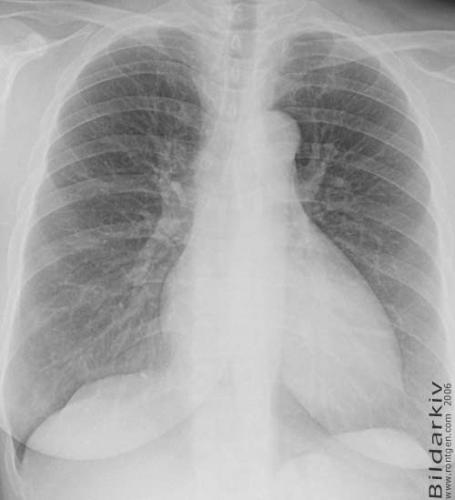

18a Lungorna kvinna 52 år

Frontal bild av lungorna på 52 årig kvinna.